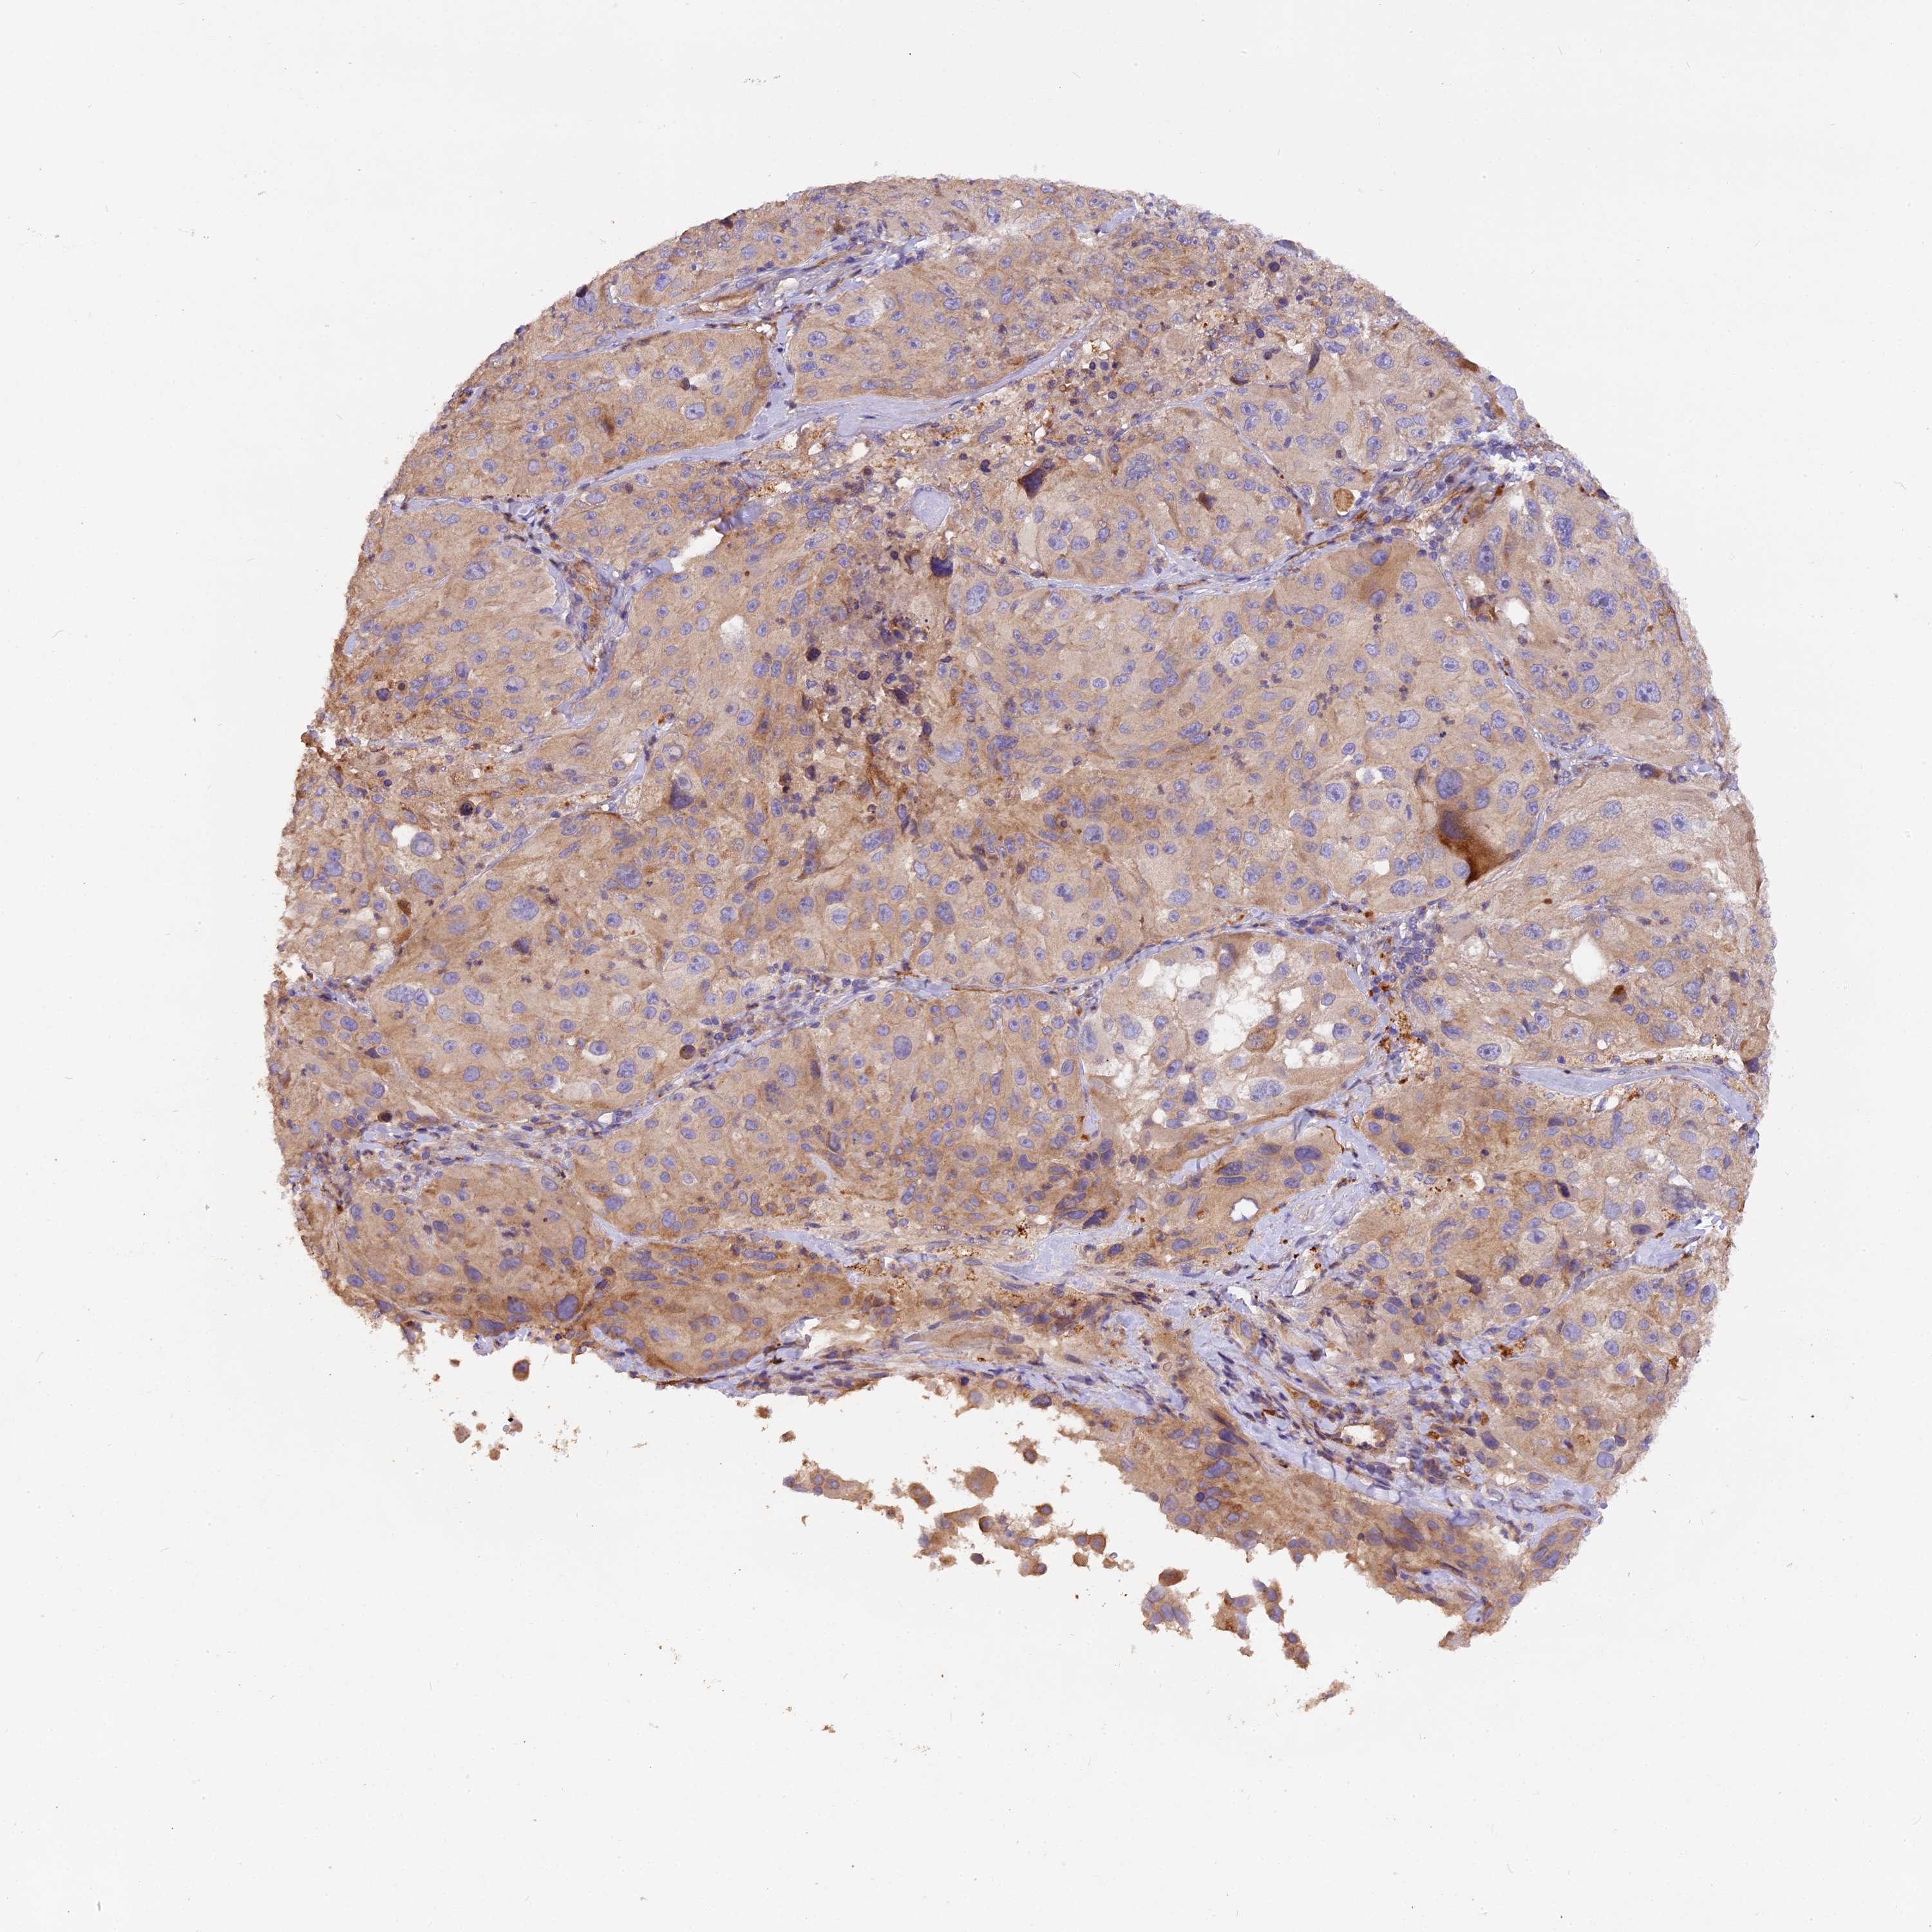

MELANOMA - Protein expressioni

A mouse-over function shows sample information and annotation data. Click on an image to view it in a full screen mode. Samples can be filtered based on level of antibody staining by selecting one or several of the following categories: high, medium, low and not detected. The assay and annotation is described here.

Note that samples used for immunohistochemistry by the Human Protein Atlas do not correspond to samples in the TCGA dataset.

Antibody stainingi

Antibody staining in the annotated cell types in the current human tissue is reported as not detected, low, medium, or high, based on conventional immunohistochemistry profiling in selected tissues. This score is based on the combination of the staining intensity and fraction of stained cells.

Each image is clickable and will lead to virtual microscopy that enables deeper exploration of all samples and also displays staining intensity scores, fraction scores and subcellular localization as well as patient and tissue information for each sample.

Antibody HPA041741

Staining

High

Medium

Low

Not detected

Intensity

Strong

Moderate

Weak

Negative

Quantity

>75%

75%-25%

<25%

None

Location

Nuclear

Cytoplasmic/membranous

Cytoplasmic/membranous,nuclear

Malignant melanoma, NOS

Malignant melanoma, Metastatic site